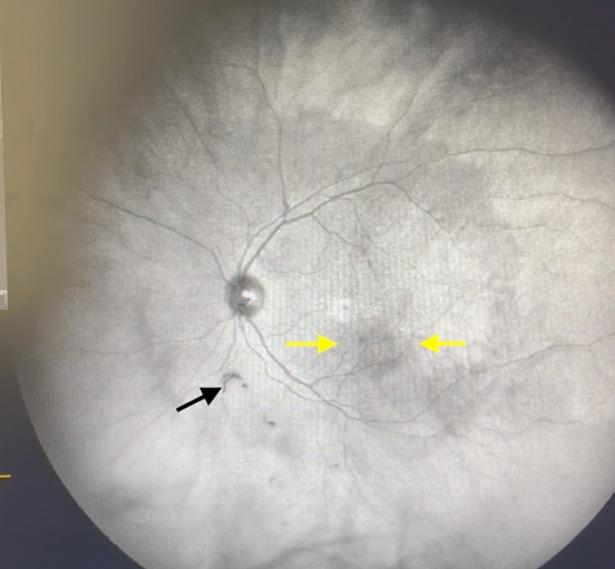

High blood sugar levels associated with diabetes can lead to damage of the blood vessels in the eyes, a condition known as diabetic retinopathy. This damage can cause bleeding in the eye, leading to the appearance of floaters.

Additionally, individuals with diabetes are at a higher risk of developing other eye conditions like vitreous hemorrhage or retinal detachment, both of which can cause floaters. It's important for people with diabetes to manage their blood sugar levels effectively and have regular eye exams to monitor and address any potential issues early on.